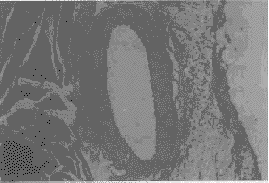

图3 支架植入6月后,支架段血管的光镜观察

可见支架去除后管壁所留的孔洞,内膜增生在支架植入处最厚,离开支架逐渐减少。支架位于增生内膜与中膜之间,支架下中膜变薄,拉长(Vergert染色,10×4)